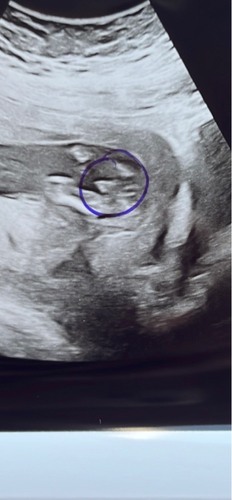

Bij ons zag je duidelijk een piemeltje uitsteken uit ‘t lichaam. Staat ook duidelijk op foto. Je moet dus wel geluk hebben dat je baby er goed voor ligt/zit. Onze baby was heel actief dus we hebben in dat half uur alle mogelijke kanten kunnen zien!

Bij onze dochter zagen we ook een 'piemeltje ' uitsteken. Dat is de nub volgens mij, en bij 13 weken zou je aan de hand van de stand kunnen bepalen of het echt een piemeltje of een clitoris wordt.

Vind het een grappige theorie, maar net als met alle theorieën zal het de ene keer kloppen en de andere keer toevallig niet🤷🏻♀️